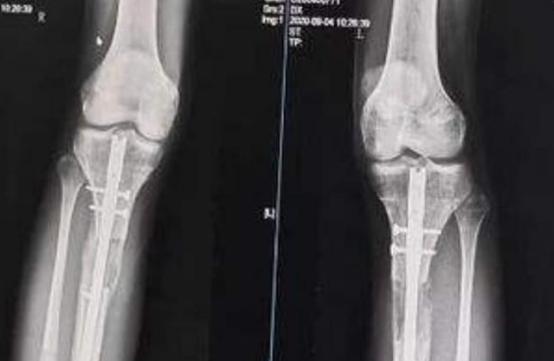

在做手术之前,医生给他进行全面的检查,最终确定术后会增加7.5厘米。

2014年9月24日,李亚诺怀着重生的心,进入了手术室。

这场手术进行了好几个小时,手术结束后,李亚诺被平安地推了出来,

医生告诉他的父母,手术很成功,

如果术后恢复得不错,明年他的身高就能达到174厘米。

在复查的时候,医生告诉他们李亚诺还要做一次手术,这次手术做完后,应该会恢复的不错。

就这样,20岁的李亚诺再次躺进手术室,这一次手术过程进展得很顺利,

然而术后李亚诺的恢复却不为理想。

在拆掉腿部支架后,他的腿部肌肉出现了病变,他再也不能像正常人一样走路了。

慢慢的,他的腿部出现变形,脚部也出现问题,总之他的恢复很糟糕。